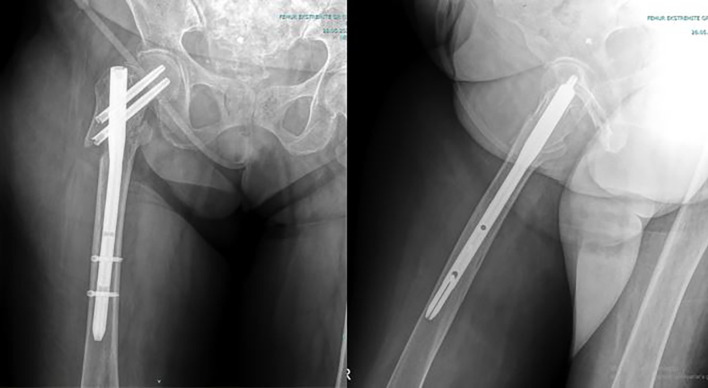

Abstract Image